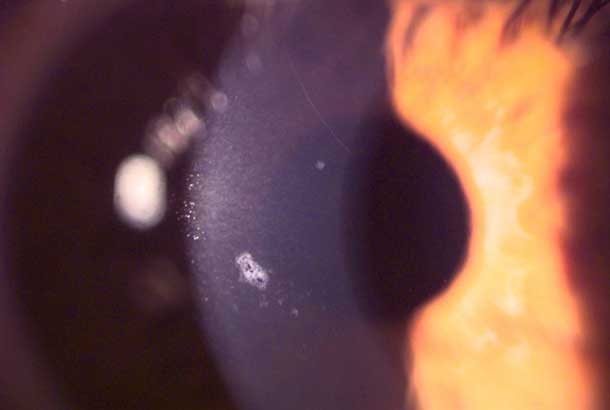

"detail": "<h2>Symptoms</h2>\n\n<ul>\n\t<li>Generally none</li>\n\t<li>May be mild irritation or hazing of vision</li>\n</ul>\n\n<h2>Signs</h2>\n\n<ul>\n\t<li>Microcysts show reversed illumination in marginal retro illumination (higher refractive index of necrotic cells)</li>\n\t<li>Vacuoles show non-reversed illumination and are larger and more rounded</li>\n\t<li>Punctate staining may be seen</li>\n</ul>\n\n<h2>Etiology</h2>\n\n<ul>\n\t<li>Microcysts are incompletely formed cells which move through the epithelium with normal cellular turnover</li>\n\t<li>Due to chronic hypoxia. Typically take several months to occur</li>\n\t<li>Can also be seen in non-CL wearers</li>\n\t<li>Small numbers of microcysts in a CL wearer is considered normal</li>\n\t<li>Vacuoles are fluid filled spaces due to chronic hypoxia</li>\n</ul>\n\n<h2>Prevalence</h2>\n\n<ul>\n\t<li>Occasional</li>\n</ul>\n\n<h2>Differential Diagnosis</h2>\n\n<ul>\n\t<li><a href=\"/condition/11\">Microcystic Edema (epithelial edema)</a></li>\n\t<li><a href=\"/condition/66\">See: Infiltrates and Opacities &ndash; Differential Diagnosis</a></li>\n</ul>\n\n<h2>Management</h2>\n\n<ul>\n\t<li>Change to high Dk/t lenses, reduce the number of nights wear/week if EW, or change to DW or DD</li>\n\t<li>May be a temporary increase in microcyst numbers after ceasing EW or changing from low Dk to high Dk EW lens</li>\n</ul>",

"images": [